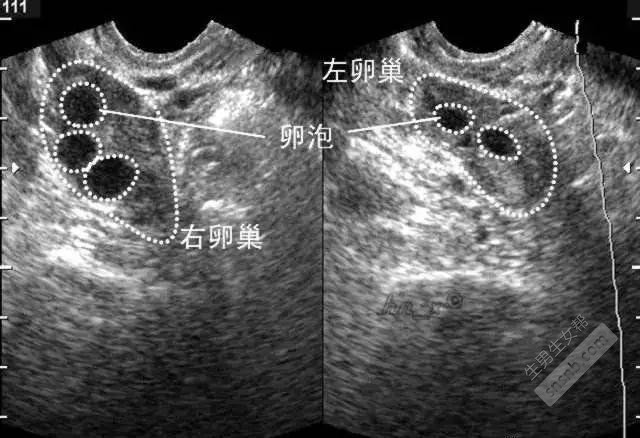

超声检查:检查基础卵泡数量。